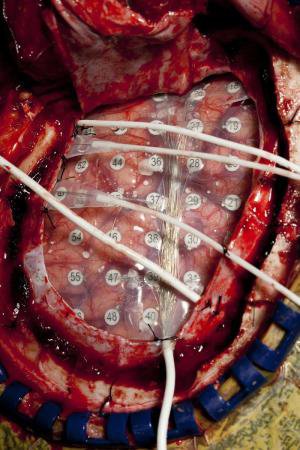

اسمیت با کمک همکارانش سیگنالهای الکتریکی ناشی از سطوح مغز چهار بزرگسال مبتلا به صرع شدید (دو مرد و دو زن) را ضبط کردند.

آنها الکترودهایی به اندازه یک دگمه را بر روی نیمکرههای چپ، راست و مرکز مغز هر یک از سوژهها قرار دادند.

محققان این عمل را بسته به اینکه تصور میشد حملات صرع بیمار از کجا ناشی میشود، انجام دادند.

این آزمایش بر روی داوطلبانی صورت گرفت که مبتلا به صرع شدید بودند و عملهای جراحی را با هدف درمان بیماریشان انجام داده بودند.